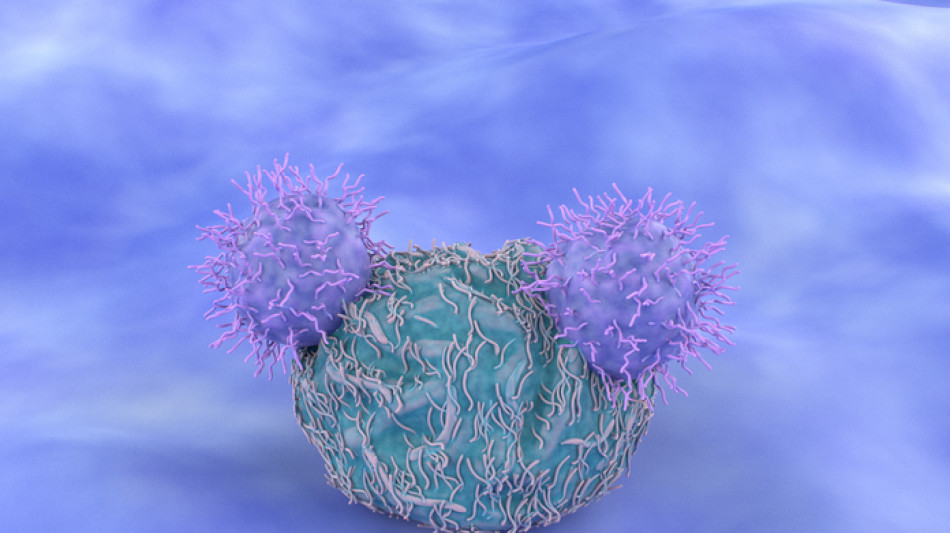

Scienziati australiani hanno 'insegnato' a cellule umane a combattere il cancro al cervello, in modo da abbattere i tassi di recidiva di uno dei più aggressivi tipi di tumore. Il trattamento immunoterapeutico del glioblastoma, sviluppato da studiosi del Queensland Institute of Medical Research guidati dall'immunologo traslazionale Rajiv Khanna, usa cellule immuni modificate geneticamente che rintracciano e uccidono le cellule cancerose che entrano nell'organismo. Il trattamento, detto CAR T cell therapy e descritto sul Journal of Immunotherapy for Cancer, va applicato in particolare dopo interventi chirurgici importanti, per prevenire recidive. Distruggendo cellule cancerose residue che possano essere sopravvissute alla citoriduzione chirurgica, le cellule immuni modificate contribuiscono a mantenere i pazienti liberi dal cancro nel lungo termine. "Il nostro obiettivo è di sviluppare questa terapia cellulare attraverso le fasi cliniche, e aiutare così a salvare vite", scrive Rajiv Khanna, coordinatore medico Queensland Institute of Medical Research. Dopo le programmate sperimentazioni, l'immunoterapia potrà essere disponibile come farmaco di serie, aggiunge.